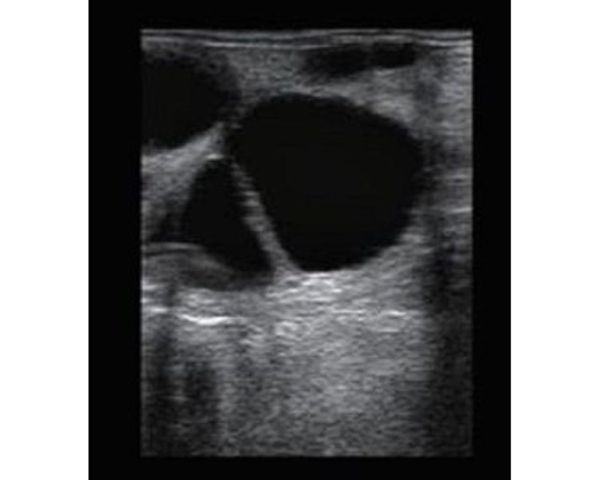

BMV S5 es un ecógrafo ultra portátil y se puede utilizar en diversas condiciones de campo, incluyendo la imagenología reproductiva bovina y equina, así como en la exploración de tendones en equinos.